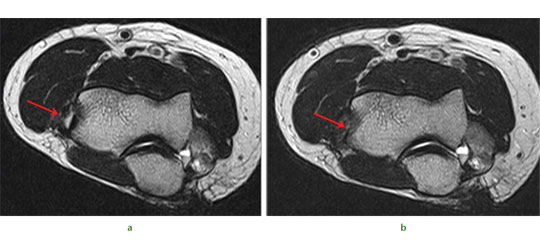

The potential of this approach is seen in the challenging case of a 51-year-old presenting with the combination of established proximal tibial malunion and ACL defi cient instability can be challenging to treat. The patient had a long standing varus malunion and a 3 cm shortening of his tibia presented with pain, instability and deformity. The patient’s medial compartment was bereft of any articular cartilage. We used a modified Taylor Spatial Frame for osteogenesis which we augmented with stem cell therapy. Application of a Taylor Spatial Frame in combination with tibial and fibular osteotomies was followed with distraction osteogenesis at a rate of 1 mm per day, commenced the day after the tibial and fibular corticotomies. We supplemented the standard treatment with stem cell therapy one week following corticotomies. Autologous PBSC were harvested from the patient and injected percutaneously into the corticotomy sites. We were able to demonstrate callus formation two weeks after distraction osteogenesis (one week after injection of PBSC, Fig.4a). Two further weekly injections of PBSC were given during the osteogenesis process and almost complete healing was seen at four months (Fig.4b). Although a similar result could have been easily achieved without the injection of PBSC there is the potential to reduce frame time and morbidity associated with extended frame wear. At final follow-up the patient did not have any equinus deformity of the ankle or a loss of initial knee movement, regaining 50° of knee range of movement following the distraction osteogenesis. A second-stage arthroscopy with subchondral drilling and allograft ACL reconstruction was performed for chondrogenesis and stabilisation of his knee. We did not see any premature closing of the corticotomy with the use of PBSC and we believe that PBSC may have a significant future role in malunion and nonunion surgery.

Fig. 4 Radiographs of a 51-yearold man who presented with left knee pain and instability, showing a) distraction osteogenesis and evidence of callus formation one week after injection of PBSC into corticotomy site (red arrow), and b) signifi cant growth of new bone after four months.